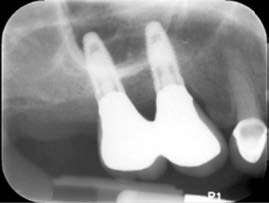

Figure 5: Pre-op X-rays showing the presence of peri-implantitis with bone loss

A 50-year-old female, nonsmoker, with noncontributory medical history came in for a routine checkup. Clinical examination revealed increased pocket depths around two maxillary implants and bleeding upon probing. The pocket depths ranged between 5 mm-8 mm facially and 4 mm-9 mm lingually. Preoperative X-ray showed circumferential bone defects around both implants (Figure 5). Diagnosis of peri-implantitis was made with the bone loss to the 3-5 threads of the implants. The possible causes include bacterial invasion of the titanium surface, occlusal trauma, and anatomical placement issues relative to the crest of bone, obstructing access for maintaining oral hygiene.